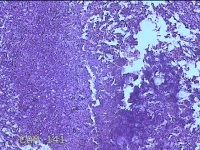

右侧窦腔内容物

性别

男

年龄

49岁

临床诊断

1.慢性鼻窦炎 2.鼻中隔偏曲 3.变应性鼻炎

一般病史

鼻塞、脓涕2月,加重伴涕中带血1周。

标本名称

大体所见

灰白暗红色不规则碎组织1.5x1.3x0.3cm一堆。